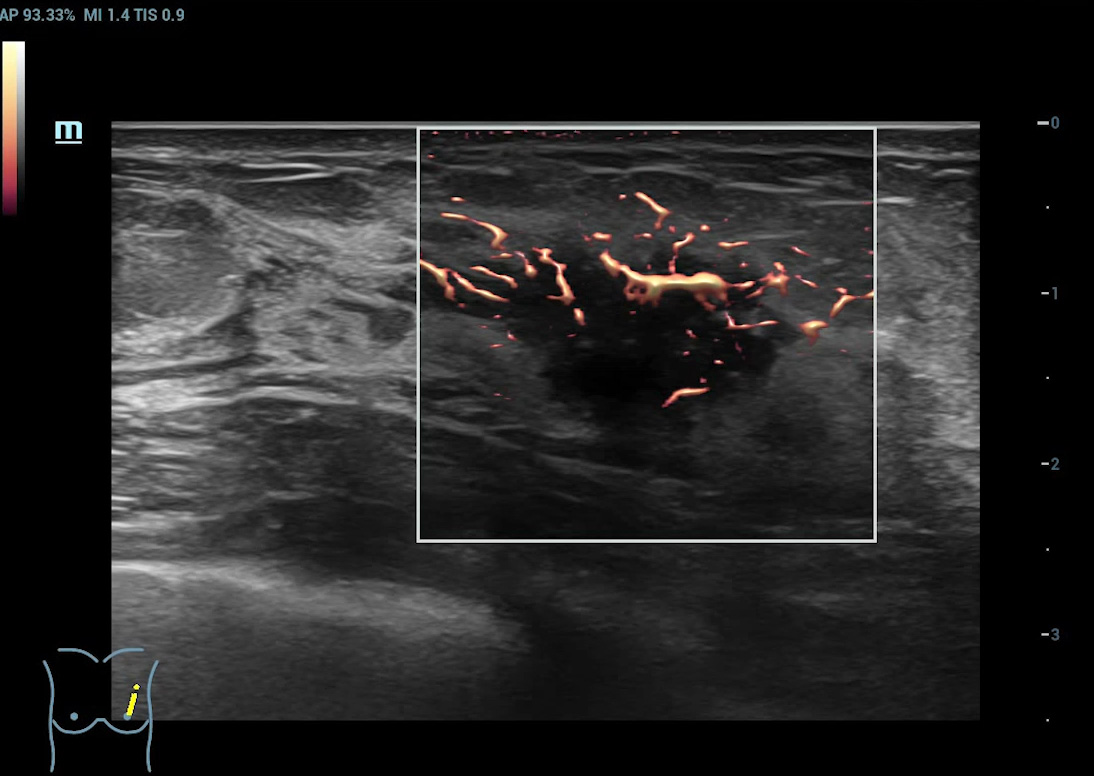

Angiografia ultramicroscû°pica (Ultra Micro Angiography, UMA)

UMA aumenta a confian?a diagnû°stica ao expandir a visibilidade dos fluxos sanguûÙneos atûˋ o nûÙvel de vasos minû¤sculos, com sensibilidade e resolu??o superiores.

pUMA ã Massa mamûÀria

Galeria de imagens

cUMA ã Massa mamûÀria

CEUS ã Massa mamûÀria